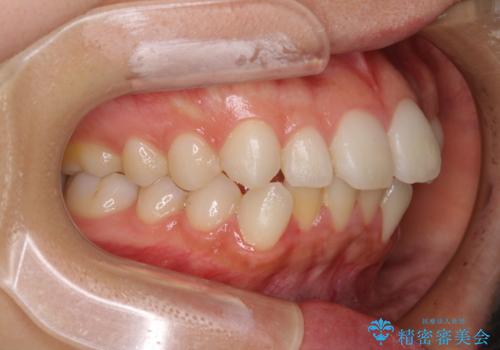

インビザライン特有の、奥歯の咬み合わせの問題もなく、しっかりと歯列を改善することができました。

舌側転位している上顎側切歯(内側に引っ込んでいる真ん中から2番目の歯)は、インビザラインが最も移動を苦手とする歯であり、これ以上の改善を望まれる場合にはワイヤー矯正、あるいはワイヤー矯正の併用をお勧めいたします。